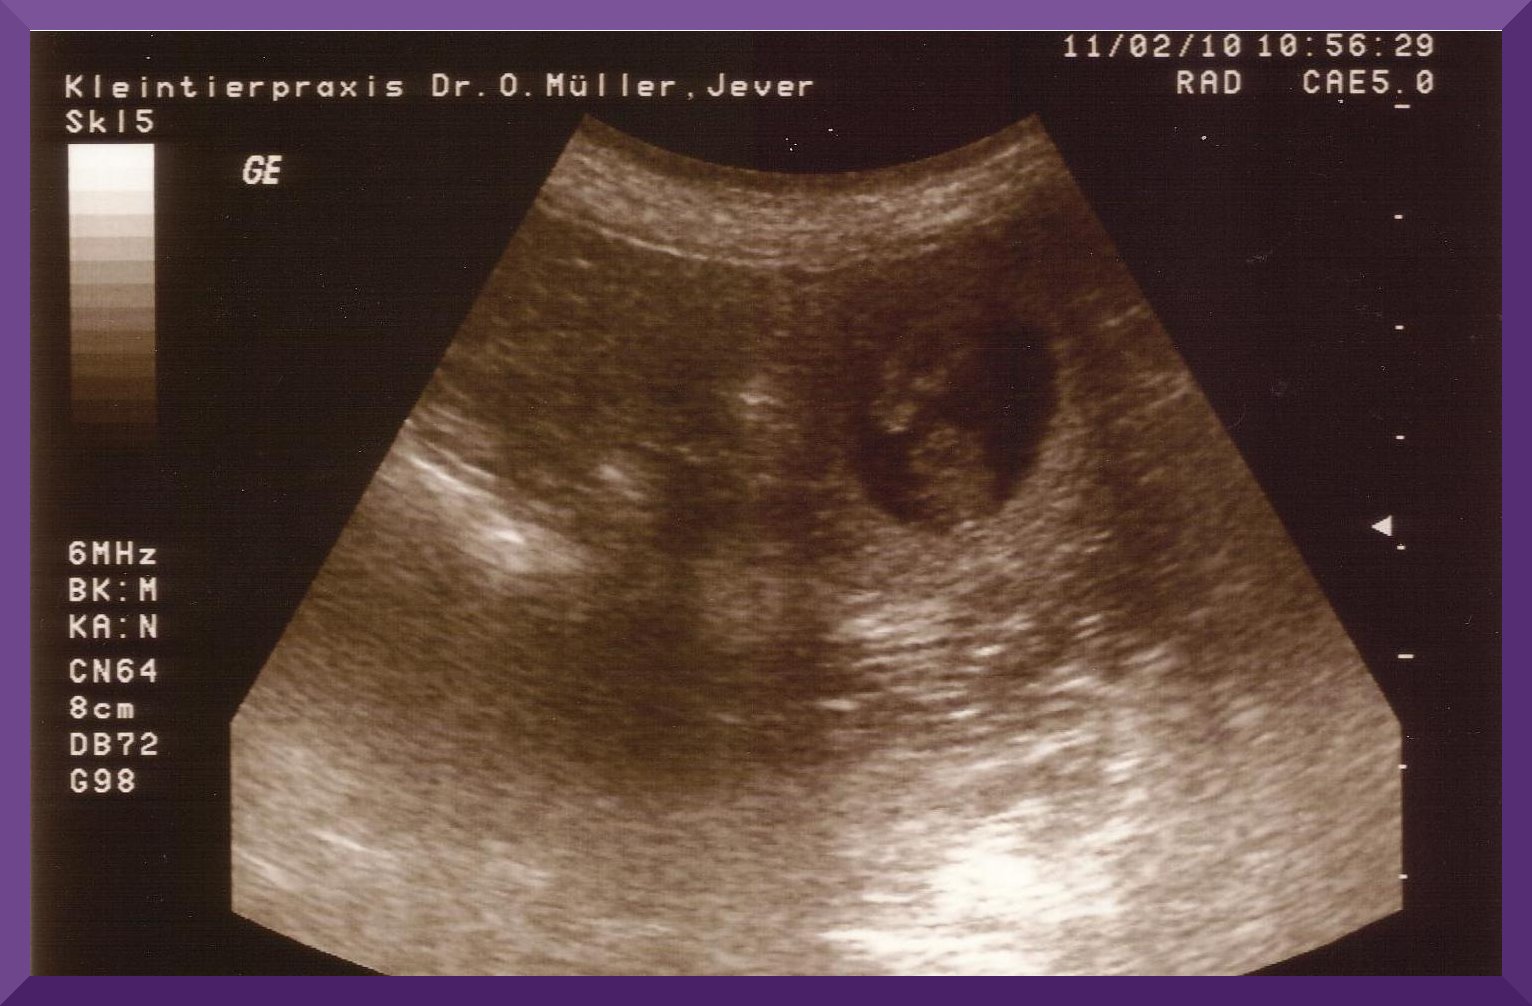

Ultraschall Lulu 2010 |